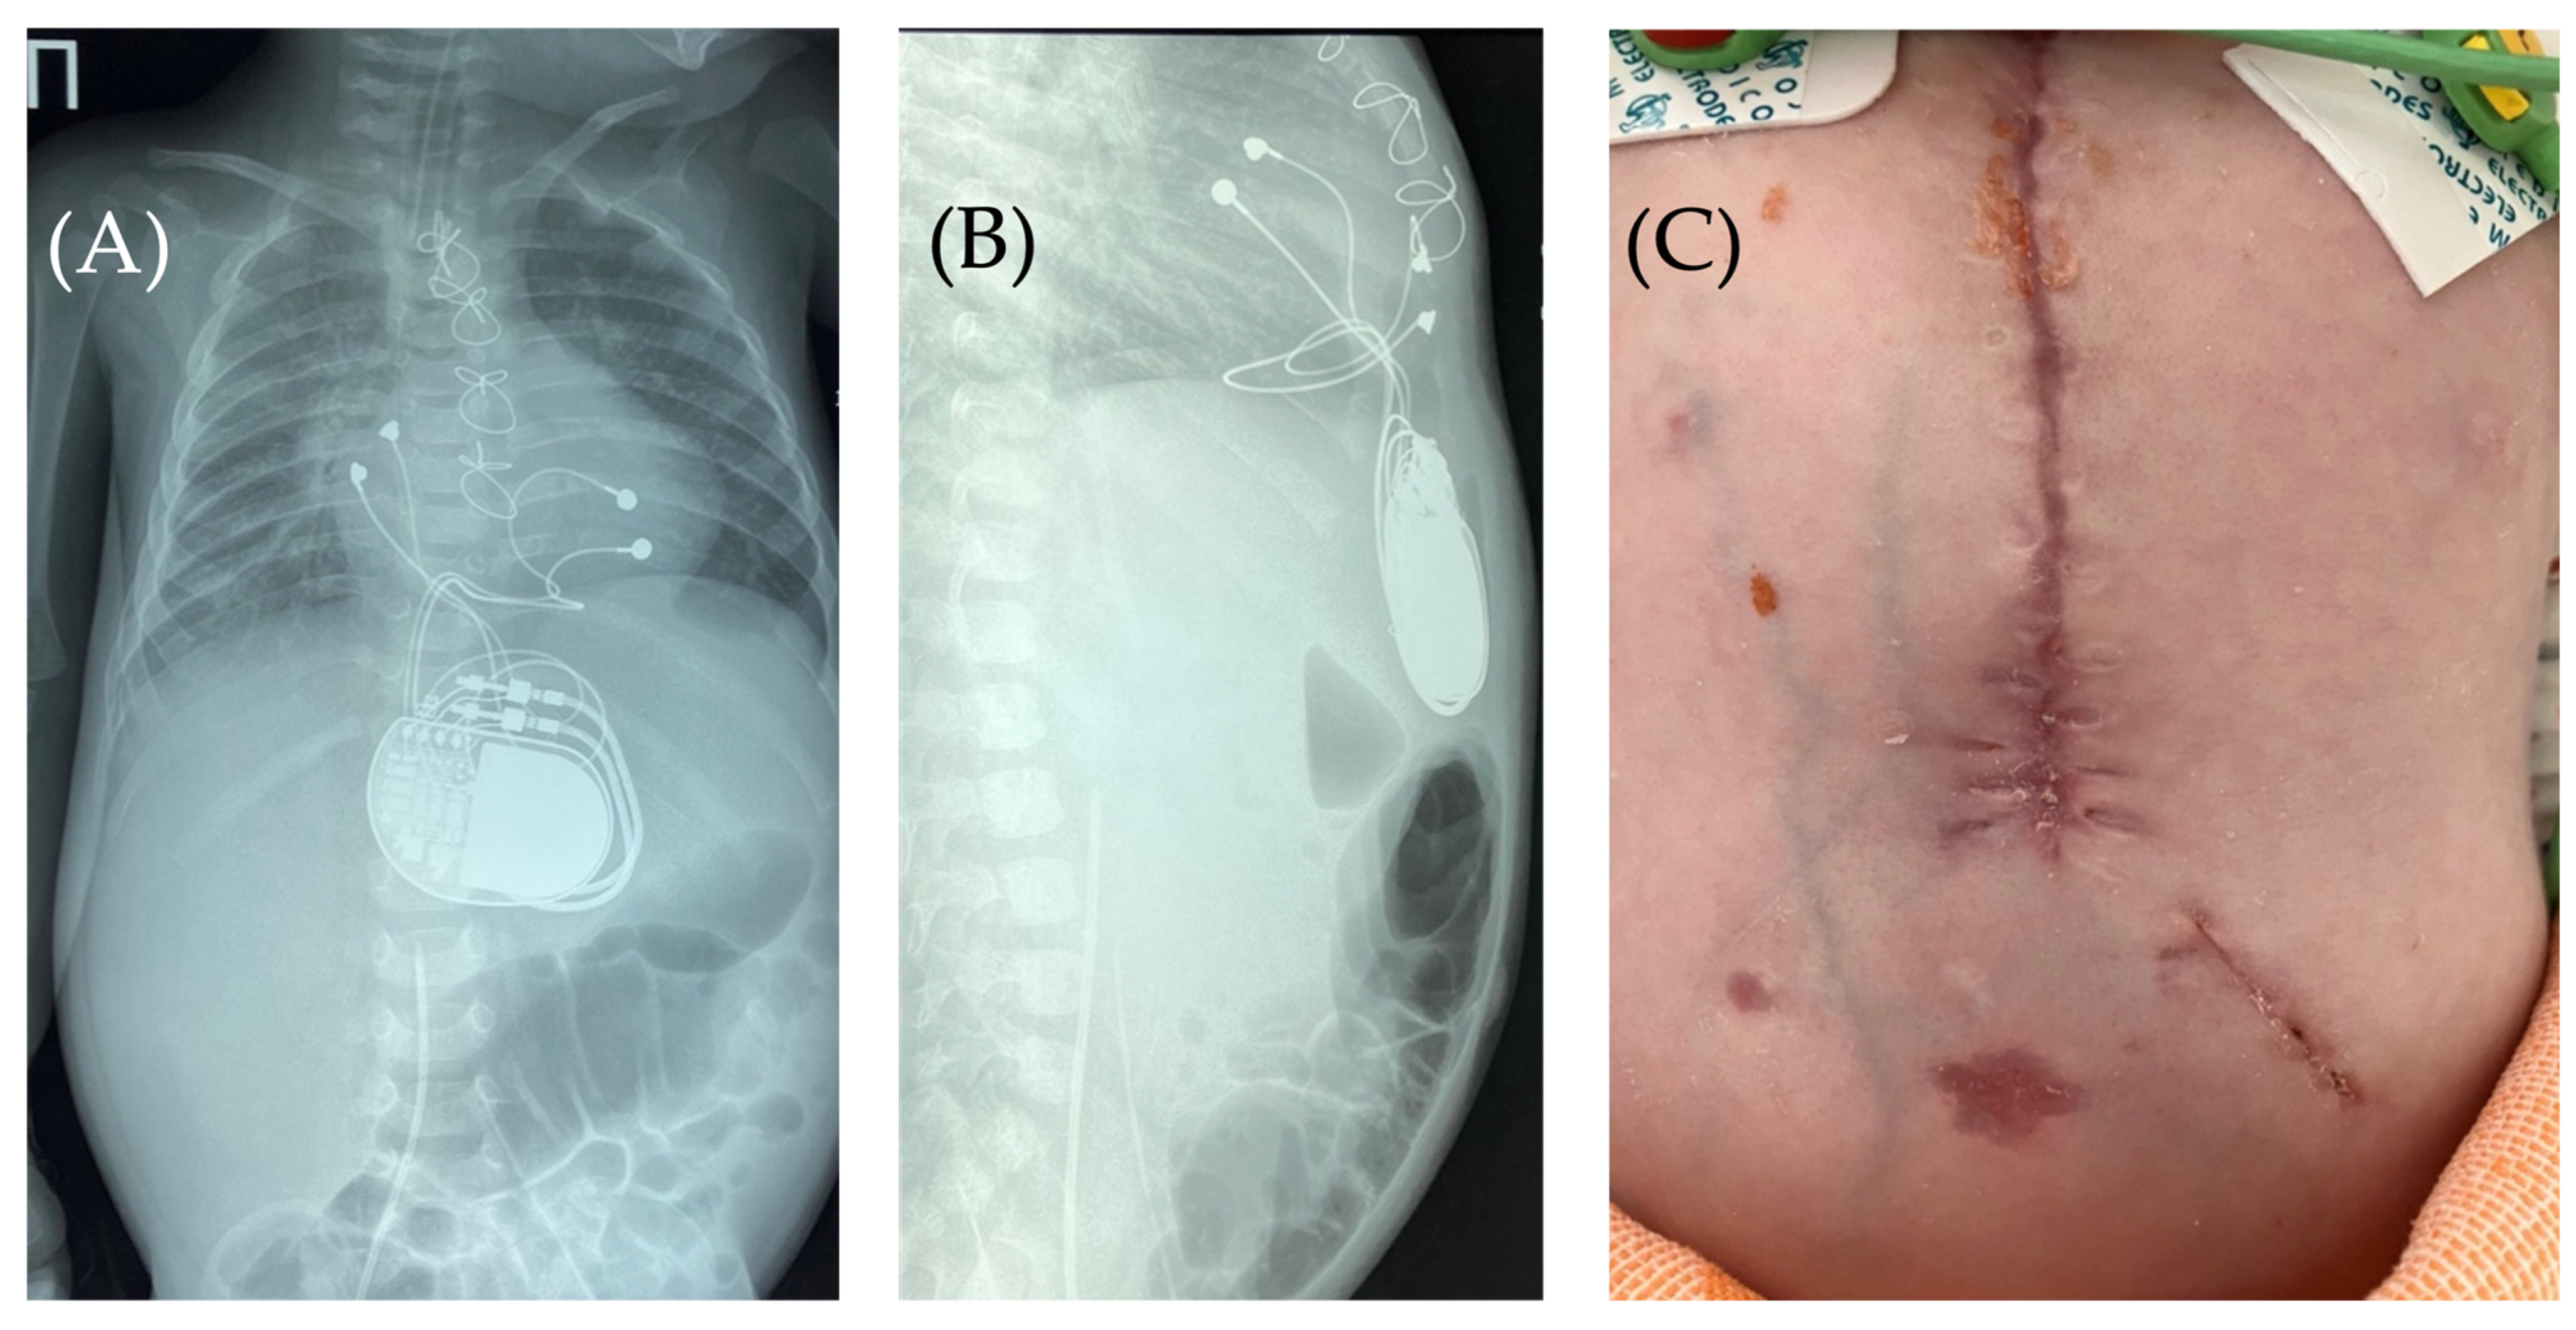

Fluoroscopy and chest and abdominal radiography revealed no signs of pneumothorax. A demarcated area of free air was visualized in the upper anterior abdominal wall along the midline, projecting to the pacemaker pocket. The passage of radiocontrast agent through the gastrointestinal tract was observed dynamically and found to be normal. No signs of hollow organ perforation or intestinal obstruction were detected (Figure 2, Figure 3 and Figure 4).

Figure 2. Chest X-ray—frontal (A) and lateral (B) view. Chest X-ray shows no pneumothorax, but pneumopericardium, pneumomediastinum and air in the pacemaker pocket site (red arrow) are present. One can also see the pacemaker electrodes (yellow arrow), the pulse generator (black asterisk), and the wire ligature (pink arrow). R: right side.